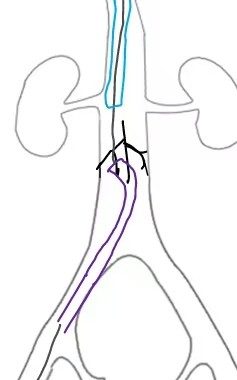

Through and through wire was achieved from popliteal to IJV and the 14fr IJV sheath was advanced past the IVCF struts to act as a protection for the basket and coring element of the ClotTriever for thrombectomy of the IVC and iliofemoral veins as several passes were made. There was satisfactory clearance of clots from the left iliofemoral veins. Aspiration of the IVCF was then performed with a FlowTriever 16 catheter but there was incomplete thrombectomy with some of the remnant clots being pushed above the IVC filter. The IJV sheath was upsized to 16F over and the sheath was used to protect the ClotTriever as it passed though the filter. The through and through Rosen wire (Cook Medical, Bloomington, Indiana) was subsequently pulled back from the IJV and cannulated into the right subclavian vein. The ClotTriever was then deployed next to the 16Fr sheath above the filter as an embolic protection device. The thrombosed IVC filter was then retrieved with a Clover snare (Cook Medical, Bloomington, Indiana). From the IJV sheath, FlowTriever disks were deployed and further thrombectomy of the remnant IVC thrombus was performed which yielded even more thrombus.

Right internal jugular vein (IJV) and popliteal vein large bore access was obtained with a 14Fr sheath and a 16Fr ClotTriever sheath respectively. Initial venogram showed extensive thrombosis from the below knee popliteal vein to the IVC filter with flow stasis of the intravenous contrast.